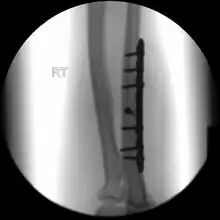

.jpg)

If the fracture is not significantly displaced, is stable, and is not associated with another fracture, it may be treated with a cast for around five to six weeks.[3] This includes fractures that are less than 50% displaced and less than 10 degrees angulated.[6]

During the recovery period healing can be followed up with x-rays.[3] Heavy lifting should be avoided.[3] After the cast has been removed exercises are encouraged and full strength is regained over time.[3] Treatment may may also be with splinting and early movement.[2]

When there is a displaced fracture or when the radioulnar joints are involved an operation is often performed, using either flexible rods or screws and plates in order to reduce the fracture and immobilise the bone.[3]